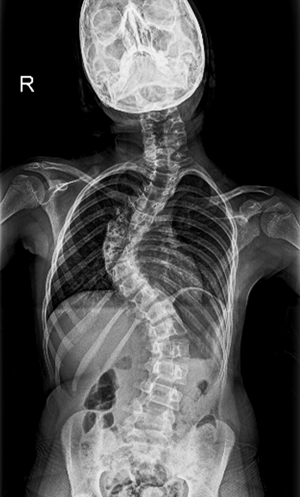

BEYOND RECOVERY : REAL STORIES

Gallery : Before - After